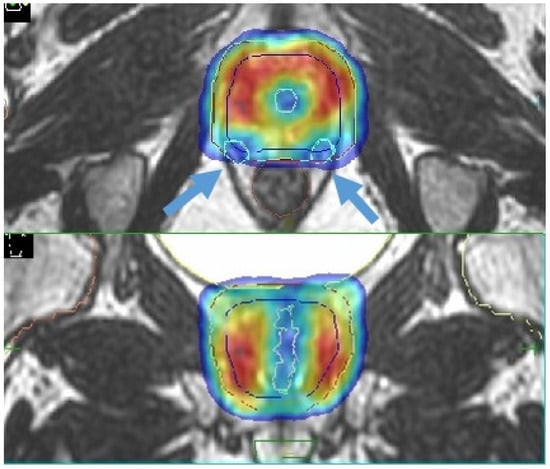

4.1. Boost of the Dominant Intraprostatic Lesion

- Cuccia, F.; Mazzola, R.; Nicosia, L.; Figlia, V.; Giaj-Levra, N.; Ricchetti, F.; Rigo, M.; Vitale, C.; Mantoan, B.; De Simone, A.; et al. Impact of hydrogel peri-rectal spacer insertion on prostate gland intra-fraction motion during 1.5 T MR-guided stereotactic body radiotherapy. Radiat. Oncol. 2020, 15, 1–9. [Google Scholar] [CrossRef] [PubMed]

- Ruggieri, R.; Rigo, M.; Naccarato, S.; Gurrera, D.; Figlia, V.; Mazzola, R.; Ricchetti, F.; Nicosia, L.; Giaj-Levra, N.; Cuccia, F.; et al. Adaptive SBRT by 1.5 T MR-linac for prostate cancer: On the accuracy of dose delivery in view of the prolonged session time. Phys. Med. 2020, 80, 34–41. [Google Scholar] [CrossRef] [PubMed]

- Alongi, F.; Rigo, M.; Figlia, V.; Cuccia, F.; Giaj-Levra, N.; Nicosia, L.; Ricchetti, F.; Sicignano, G.; De Simone, A.; Naccarato, S.; et al. 1.5 T MR-guided and daily adapted SBRT for prostate cancer: Feasibility, preliminary clinical tolerability, quality of life and patient-reported outcomes during treatment. Radiat. Oncol. 2020, 15, 1–9. [Google Scholar] [CrossRef]

- Alongi, F.; Rigo, M.; Figlia, V.; Cuccia, F.; Giaj-Levra, N.; Nicosia, L.; Ricchetti, F.; Vitale, C.; Sicignano, G.; De Simone, A.; et al. Rectal spacer hydrogel in 1.5T MR-guided and daily adapted SBRT for prostate cancer: Dosimetric analysis and preliminary patient-reported outcomes. Br. J. Radiol. 2021, 94, 20200848. [Google Scholar] [CrossRef] [PubMed]